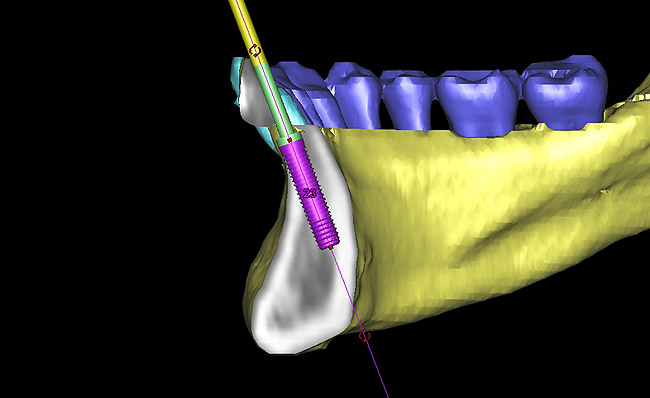

Following the first goal of orthodontia—moving tooth No. 22 to a proper functional and anatomical position—a periodontal reevaluation was performed, demonstrating an improvement in short- and long-term tooth prognosis. At this time, the decision was made to abort continual extrusion of teeth Nos. 21 and 22, although some attachment level discrepancy remained between Nos. 21 and 22 (Figure 14). Implant diagnostics ensued and included mounted study models and a diagnostic wax-up. A scanning appliance was created to demonstrate the desired prosthetic outcome requirements, and the patient was referred for computed tomography (CT) scans. CT scan assessment demonstrated successful orthodontically directed GBR to allow implant placement (Figure 15 through Figure 16). Only minor GBR therapy would be needed and could be accomplished simultaneously with implant installation. Guided implant placement occurred, using an open flap approach (Figure 17). During surgery, root dehiscences were noted on teeth Nos. 21, 22, 24, and 25, as well as the anticipated dehiscence following implant placement at No. 23 (Figure 18). A positioning reference (index) was secured after implant placement to facilitate a provisional prosthesis at stage II surgery. Cortical perforations then were placed adjacent to the implant to encourage angiogenesis (Figure 18), and mineralized freeze-dried bone allograft enhanced with platelet-derived growth factor was placed over the dehiscences for purposes of guided tissue regeneration and GBR (Figure 19). A highly resorbable collagen membrane was placed to stabilize the allograft. The flap was coronally repositioned, and primary-intention wound healing was achieved (Figure 20 and Figure 21). Following 4 months of stage I surgery, implant uncovery and immediate provisionalization were performed in conjunction with connective tissue grafting. Final orthodontic tooth movement then ensued, using the implant as anchorage to optimize end-tooth movements, interroot separation, and the cuspid-protected occlusal scheme. A final impression then was secured, and a zirconia abutment (Figure 22) with an all-ceramic restoration was fabricated for the prosthetic phase completion of No. 23 (Figure 23 through Figure 25).

Figure 15  Presurgical 3-dimensional CT scan diagnostic planning for implant No. 23. Note the anticipated dehiscence at the facial aspect of the implant.

Figure 15

Figure 16  A cross-sectional view of postorthodontic site development at No. 23 position. Sufficient bone has been developed to accommodate implant placement in an optimal prosthetic position. Simultaneous GBR is planned at the coronal most portion of the implant per anticipated dehiscence.

Figure 16